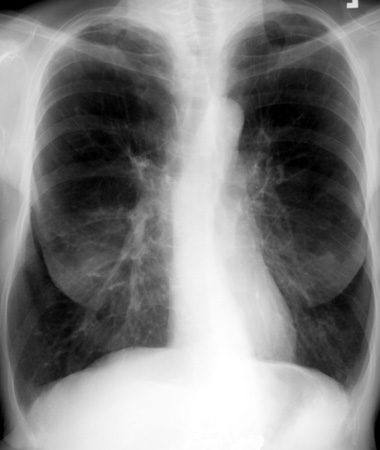

Какая конфигурация сердца представлена на данной рентгенограмме// аортальная// митральная// трапециевидная// шаровидная// +обычная